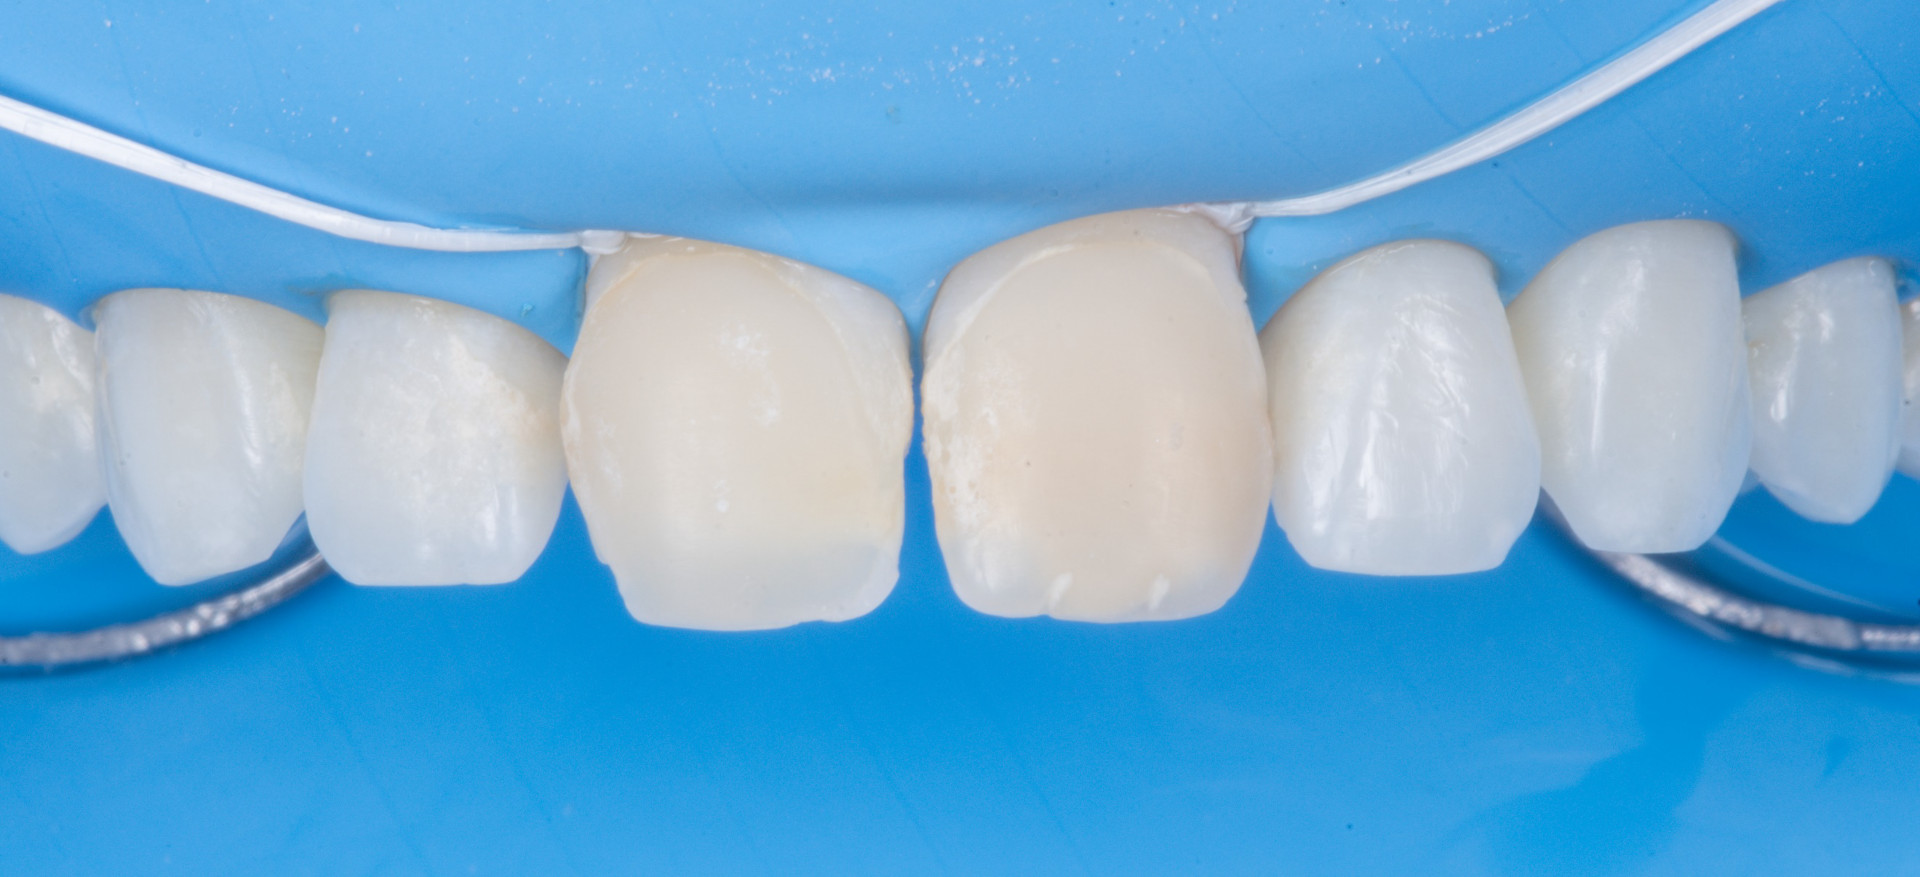

Afin d’optimiser le confort opératoire et la fiabilité du procédé de collage, après une anesthésie locale un champ opératoire est placé sur un champ large pour permettre la mise en place de la clef d’injection, ici de 15 à 25 (Digue Nictone Médium).

Fig. 6 : Mise en place du champ opératoire (Digue + ligatures teflonnées).

Remarque : d’expérience personnelle, lors de la pose du champ opératoire, il est important de privilégier une digue apportant suffisamment de rétraction gingivale mais sans être trop épaisse pour permettre l’insertion complète en butée de la clef d’injection.